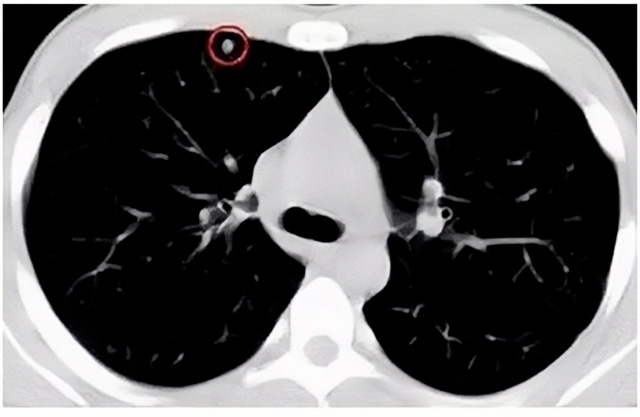

移動CT體檢車可以檢查肺結節(jié)發(fā)現早期肺癌

移動CT體檢車可以做肺部檢查。隨著多層螺旋CT肺部低劑量掃描的臨床應用,目前很多人選擇肺部CT作為常規(guī)檢查項目,較大地提高了肺結節(jié)的檢出率。如果檢查發(fā)現肺部有肺結節(jié)是磨玻璃型的,小于5mm的微小結節(jié),大部分都是良性的。如果達到1CM以上的,很有可能有肺癌的機率。根據其內密度不同可分為磨玻璃結節(jié)、實性結節(jié)、部分實性結節(jié)。根據其大小可分為肺大結節(jié)、小結節(jié)和微小結節(jié)。如果是炎癥性肺結節(jié),幾個月后復查有變化變小就不用做手術。如果CT再次復查結節(jié)沒有變化,沒有縮小就需要升級做病例檢查。病理檢查的確診性是最高的。是有沒患癌的標準。檢查發(fā)現早的話,規(guī)范手術治療,手術后5年的存活率很高的。肺癌這個要早發(fā)現早治療。

現在的移動CT體檢車的分辨率比X光高,CT掃描的圖像越來越薄顯像更清晰,檢查更準確。得到了普及,肺結節(jié)的測出率很高的。但是顯浩告訴大家,肺結節(jié)不等于肺癌。雖然很多是良性,但是很多肺癌都是肺結節(jié)發(fā)展來的。 必須定期檢查復查。磨玻璃結節(jié),肺癌的機率較高。肺癌是惡性腫瘤病死率最高的。除了環(huán)境,遺傳,等因素。吸煙,從事煙霧工作行業(yè)的人員比較危險。發(fā)病比例高。肺部疾病早發(fā)現早治療,依舊是肺部疾病的治療標準。

一旦CT檢查發(fā)現肺結節(jié),若不規(guī)律復查,檢查等同于白檢。所以在復查中,如果結節(jié)中發(fā)現有增大的趨勢,或大小發(fā)生了變化,我們必須提請注意及時治療,不要掉以輕心。移動CT體檢車的普及化,讓肺部檢查更準確更高效。發(fā)現肺結節(jié)時,及時就醫(yī)并進行專業(yè)評估是確保準確分類和采取適當措施的關鍵。